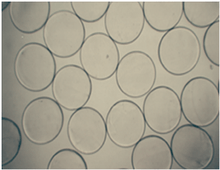

Cellulose sulphate is derived from cotton and, once processed appropriately, can be used as a biocompatible base in which to suspend cells. When the poly-anionic cellulose sulphate solution is immersed in a second, poly-cationic solution (e.g. pDADMAC), a semi-permeable membrane is formed around the suspended cells as a result of gelation between the two poly-ions. Both mammalian cell lines and bacterial cells remain viable and continue to replicate within the capsule membrane in order to fill-out the capsule. As such, in contrast to some other encapsulation materials, the capsules can be used to grow cells and act as such like a mini-bioreactor. The biocompatible nature of the material has been demonstrated by observation during studies using the cell-filled capsules themselves for implantation as well as isolated capsule material.[44] Capsules formed from cellulose sulphate have been successfully used, showing safety and efficacy, in clinical and pre-clinical trials in both humans and animals, primarily as anti-cancer treatments, but also exploring possible uses for gene therapy or antibody therapies.[4][45][46][47][48] Using cellulose sulphate it has been possible to manufacture encapsulated cells as a pharmaceutical product at large scale and fulfilling Good Manufacturing Process (cGMP) standards. This was achieved by the company Austrianova in 2007.[49]